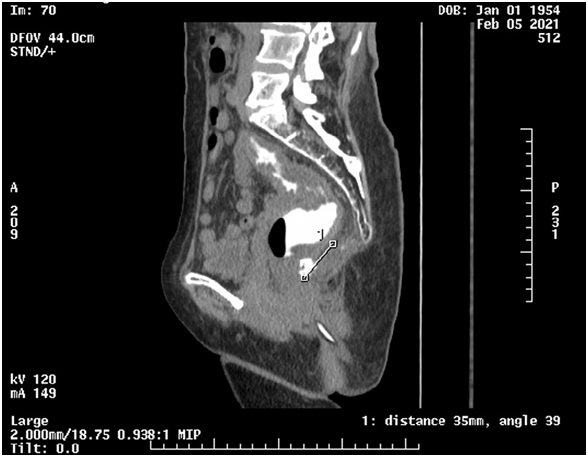

L’IRM du 27/1/2021 et le CT. Scan du 5/2/2021 (fig 4) décrivaient la tumeur de 3,5 cm sur son grand axe dont le pole inférieur était calcifié avec adhérence au bas rectum sans lésions abdominales ou autres. Le dosage des marqueurs tumoraux était dans les normes: CEA : 1.74 ng/ml et CA 19-9 16 UI/ml

Figure4)Tumeur faisant 3,5cm retro rectale